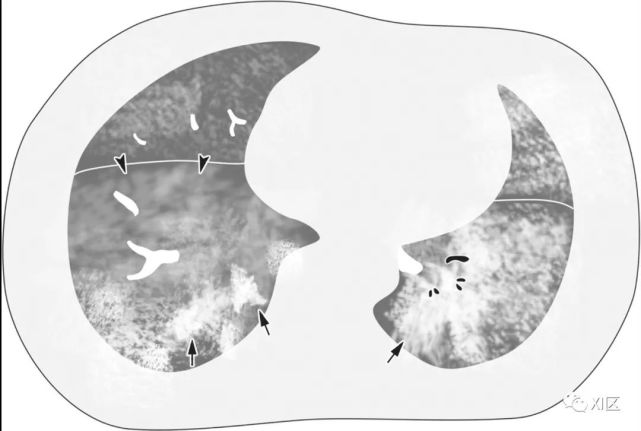

图14 一位22岁女性感染前1个月因急性淋巴细胞白血病接受单倍体相合骨髓移植治疗,有发热,诊断为 HPIV病毒性肺炎。

在主支气管水平(上)和叶间区水平(中上)的初始轴位胸部CT图像显示沿支气管血管束和轻度支气管壁增厚(箭头)的多灶性不明确结节性GGO病变(箭)。中性粒细胞减少持续存在。(中下,下)随访10天后获得的轴位胸部CT图像显示病变的范围和强度增加,并沿支气管血管束增加不规则的实变结节(箭)。尽管进行了重症监护,该患者仍然死亡。

Koo H J , Lim S , Choe J , et al. Radiographic and CT Features of Viral Pneumonia[J]. Radiographics, 2018, 38(3):719-739.